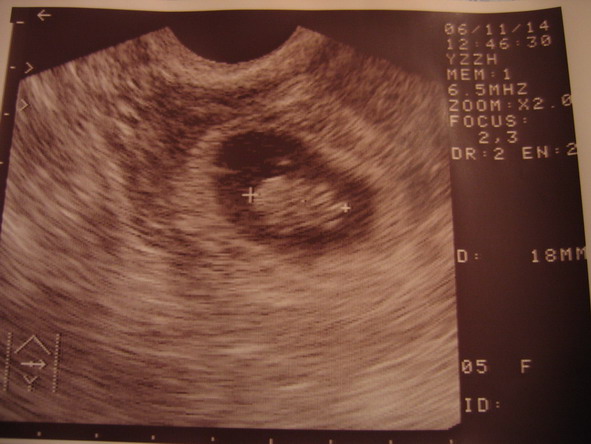

Hát, B baba nincs, teljesen eltűnt… :( De A baba van, nagyon is :D:D:D Nagyon szépen fejlődik, CRL: 18 mm :D:D És, képzeljétek: láttuk mozogni, kalimpált-úszkált - fantasztikus volt :):):):):):):) Úgyhogy nagyon boldog vagyok, ez a hír és ez a látvány kárpótolt mindenért :) Csodás volt. Kaptam képet is, bár elég gyengus az ottani UH, de persze azért felteszem :D

Korának megfelelő a mérete. Jaj, lányok, én annyira boldog vagyok, el sem hiszitek!!!! :):):):)

A következő UH: 12.04. ekkor már betöltött 12 hetes terhes leszek, és a kórházba kell mennem, ott jobb az UH és akkor már mérnek minden félét :D